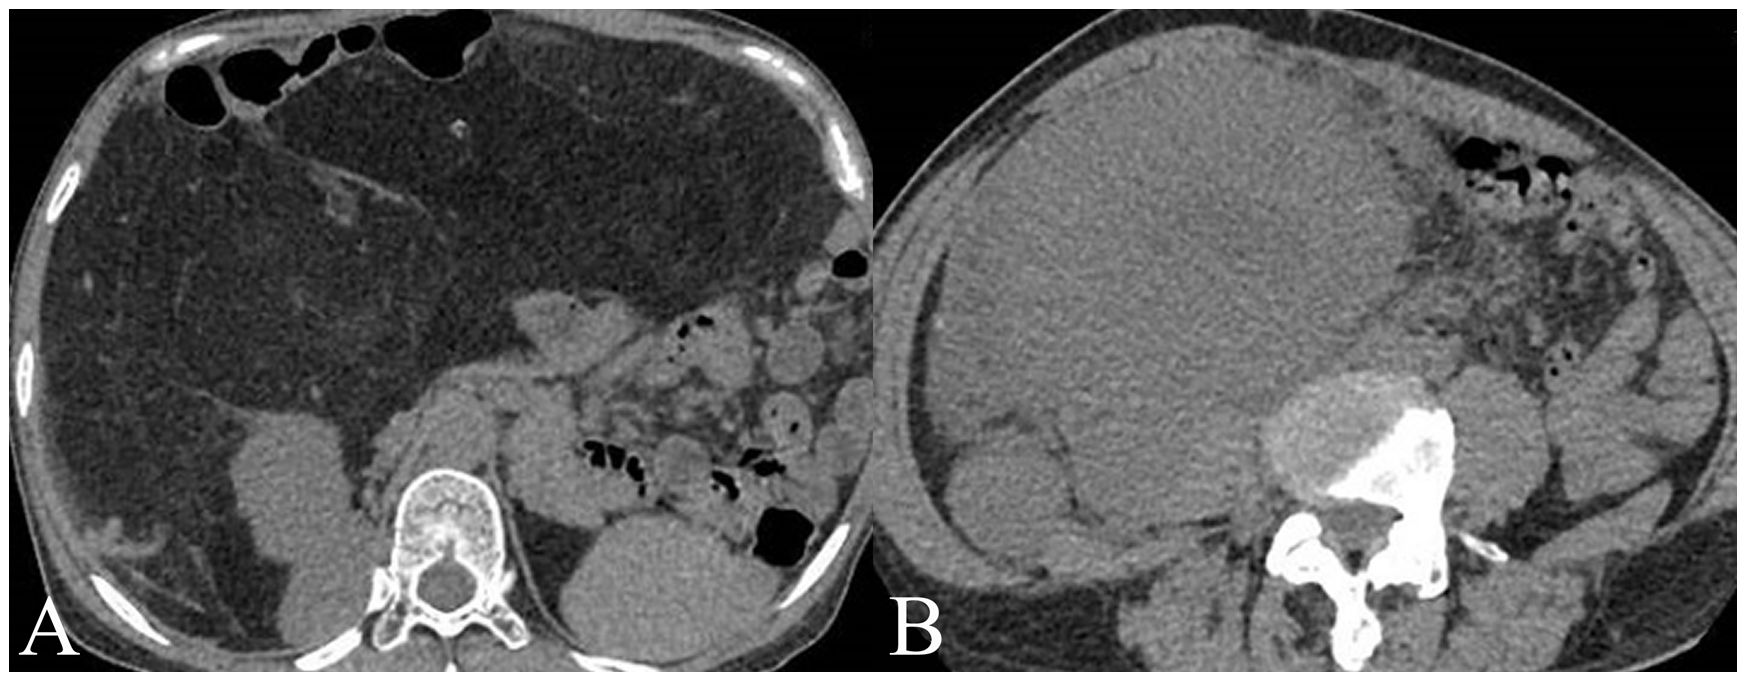

For the training set, among WDLPS cases, radiologists classified 19 cases (61.3%) correctly as WDLPS and 12 cases (38.7%) incorrectly as DDLPS. For DDLPS cases, radiologists correctly identified 43 cases (87.8%) as DDLPS, while 6 cases (12.2%) were incorrectly classified as WDLPS. For the validation set, among WDLPS cases, radiologists classified 7 cases (53.8%) correctly as WDLPS and 6 cases (46.2%) incorrectly as DDLPS. For DDLPS cases, radiologists correctly identified 20 cases (95.2%) as DDLPS, while 1 cases (4.8%) were incorrectly classified as WDLPS. Two cases demonstration is shown in Figure 2.

Figure 2. Two cases examples of histology confirmed well-differentiated liposarcoma (WDLPS) and dedifferentiated liposarcoma (DDLPS). (A) A WDLPS located in the upper abdomen, has clear boundaries with fat-like content, pushing the surrounding tissues. (B) A DDPLS located in the right lower abdomen, with unclear separations from surrounding tissues with solid content invading the right psoas major muscle.